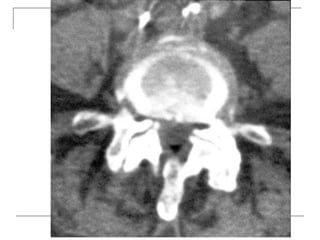

CT Scan

       better visualization of bone pathology (eg.

cortical destruction)

     fracture

     tumor

CT Scan  better visualization of bone pathology (eg. cortical destruction)  fracture  tumor